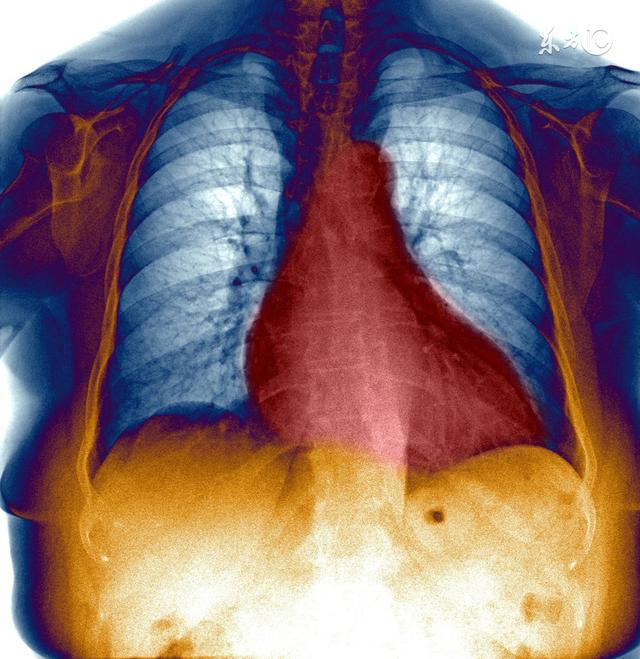

La cardiomyopathie hypertrophique est très effrayante. Pourquoi ? Parce que l'hypertrophie du muscle cardiaque signifie que les cavités cardiaques sont très petites. Si les cavités cardiaques sont petites, le cœur peut contenir moins de sang, et moins de sang peut être éjecté, et tous les organes du corps ont besoin d'un apport de sang, alors comment cette quantité de sang peut-elle être suffisante ? Le corps envoie alors au cœur l'ordre d'accélérer l'éjection du sang, ce qui fait que le cœur bat plus vite et que le muscle cardiaque se contracte plus fort pour comprimer le sang et l'éjecter.

Il existe une tentative très simple pour expliquer ce qui arrive à un muscle lorsqu'il est utilisé pendant une longue période. Le muscle s'épaissit, de la même manière que le myocarde du cœur travaille davantage, le myocarde compense en s'épaississant, ce qui réduit encore les cavités du cœur.

Le cœur lui-même a besoin d'un apport sanguin. Lorsque le cœur se contracte, les artères coronaires sont ischémiques, les cavités cardiaques contiennent moins de sang et le cœur subit des modifications ischémiques, ce qui provoque l'apparition de l'angine de poitrine.

De même, si le sang ne pénètre pas suffisamment dans le cœur, il s'accumule dans les poumons, ce qui entraîne un œdème pulmonaire et des difficultés respiratoires.